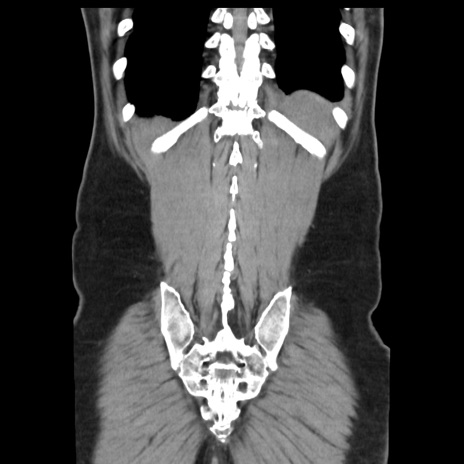

症例16(冠状断像)